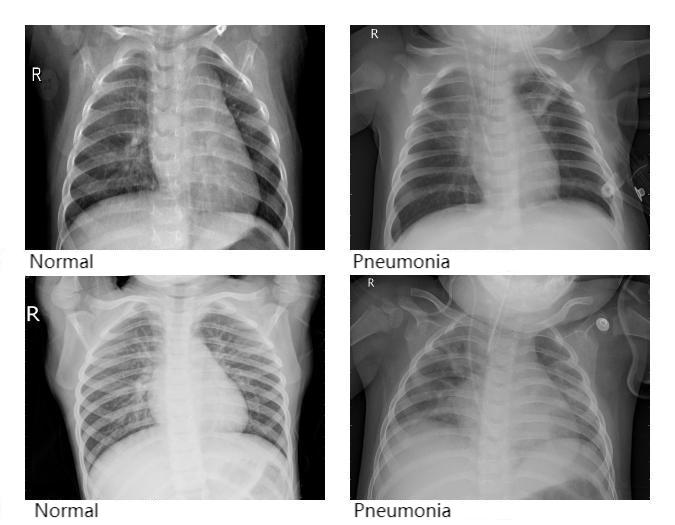

The dataset used in this study was collected from chest X-ray images, consisting primarily of radiographs from both healthy individuals and patients diagnosed with pneumonia. All images were grayscale. In total, 5,840 chest X-ray images were included. The dataset was divided into two folders, namely train and test, containing 5,216 and 624 images, respectively. Each folder was further divided into two subfolders labeled NORMAL and PNEUMONIA. Specifically, the train folder contained 3,875 images under PNEUMONIA and 1,341 images under NORMAL, while the test folder contained 390 PNEUMONIA images and 234 NORMAL images. Figure 1 illustrates several representative samples from the dataset, where NORMAL indicates a healthy condition and PNEUMONIA indicates the presence of pneumonia.